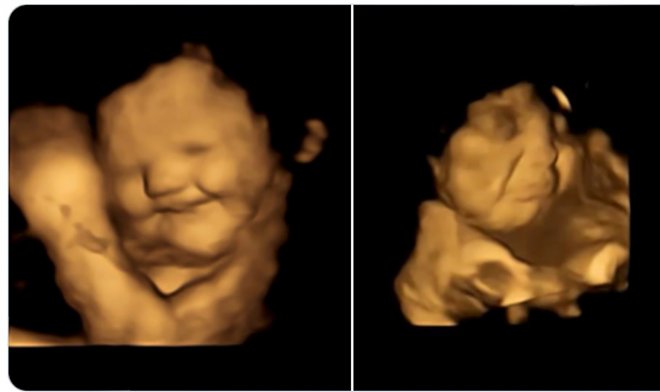

Die Studie verwendete eine fortschrittliche 4D-Ultraschall-Scantechnologie, die es ermöglicht, sehr detaillierte Bilder des Fötus zu erstellen. An dem Experiment nahmen etwa hundert Frauen im letzten Trimester der Schwangerschaft teil. Die Ultraschalluntersuchung dauerte 25 Minuten, um das fötale Verhalten maximal zu verfolgen und Fehlreaktionen auszuschließen.

Die Frauen bekamen Pillen mit Grünkohl- und Karottenpulver. Ersteres hat einen bitteren Geschmack, letzteres wird als süß empfunden, obwohl es keinen Zucker enthält. Als Ergebnis zeichnete der Scanner eine deutliche Reaktion des Fötus auf – seine Gesichter runzelten oder lächelten als Reaktion auf den bitteren bzw. süßen Geschmack. Die Daten wurden an einer Kontrollgruppe getestet, die keine speziellen Aromen erhielt.